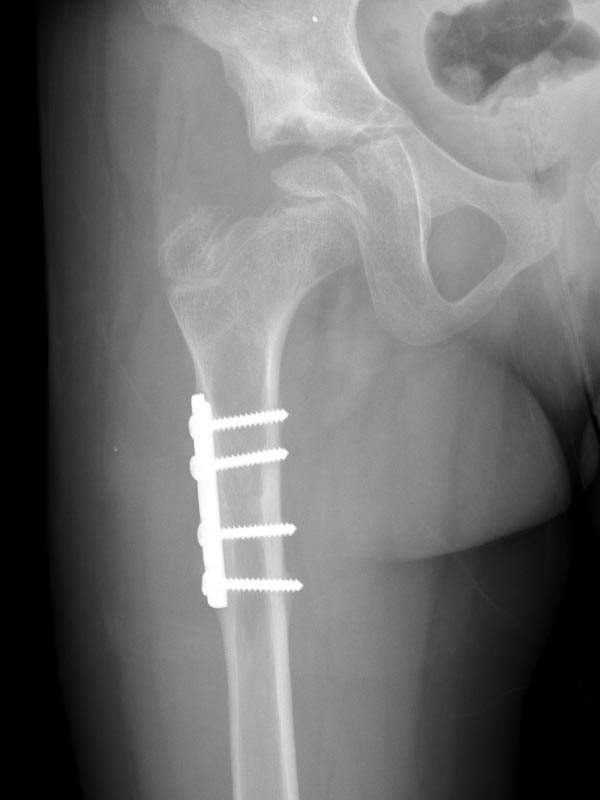

Caso No. 4 - Deslizamiento epifisiario

Preoperación

Posoperación

Deslizamiento Epifisiario Femoral

Diagnóstico: deslizamiento epifisiario femoral proximal crónico derecho

Tratamiento quirúrgico: luxación quirúrgica de la cadera derecha y realineación de la cabeza femoral.